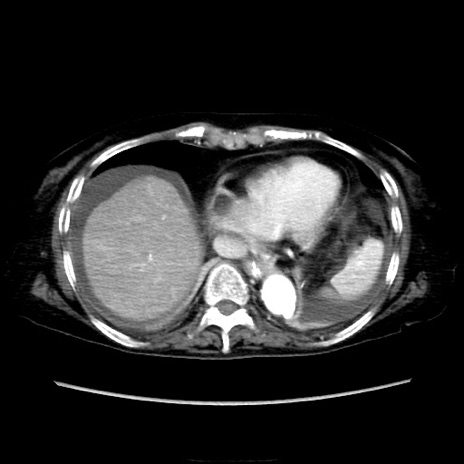

症例40(横断像)

【症例】90歳代女性

【主訴】腹痛・嘔吐

【現病歴】 食欲低下、嘔吐があり昨日他院受診。肺炎と診断され入院となる。入院後より腹部全体に圧痛あり。胃管留置され経過みていたが、症状持続するため、

当院転院となる。

【既往歴】胸椎圧迫骨折、胆石症

【身体所見】腹部:中央に激痛あり、圧痛あり、反跳痛不明

【データ】WBC 17100、CRP 18.82

他院CT